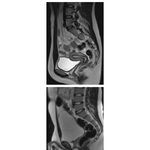

• Pelvic Scans: Sagittal T2-Weighted MRIs

379. Pelvic Scans: Sagittal T2-Weighted MRIs